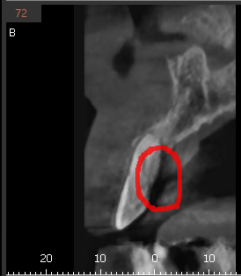

ct 사진을 분석해보니

빨간색 동그라미 부분을 봐주세요.

까만 부분이 보이시죠?

이 부분이 뼈가 녹은 부위인데

한쪽 벽면이 다 녹았습니다.

윗니 앞니 흔들림 증상 외에도

뼈가 치아를 붙잡아주지 못해

치아가 자꾸 내려오고

뻐드러져 보이는 현상 발생